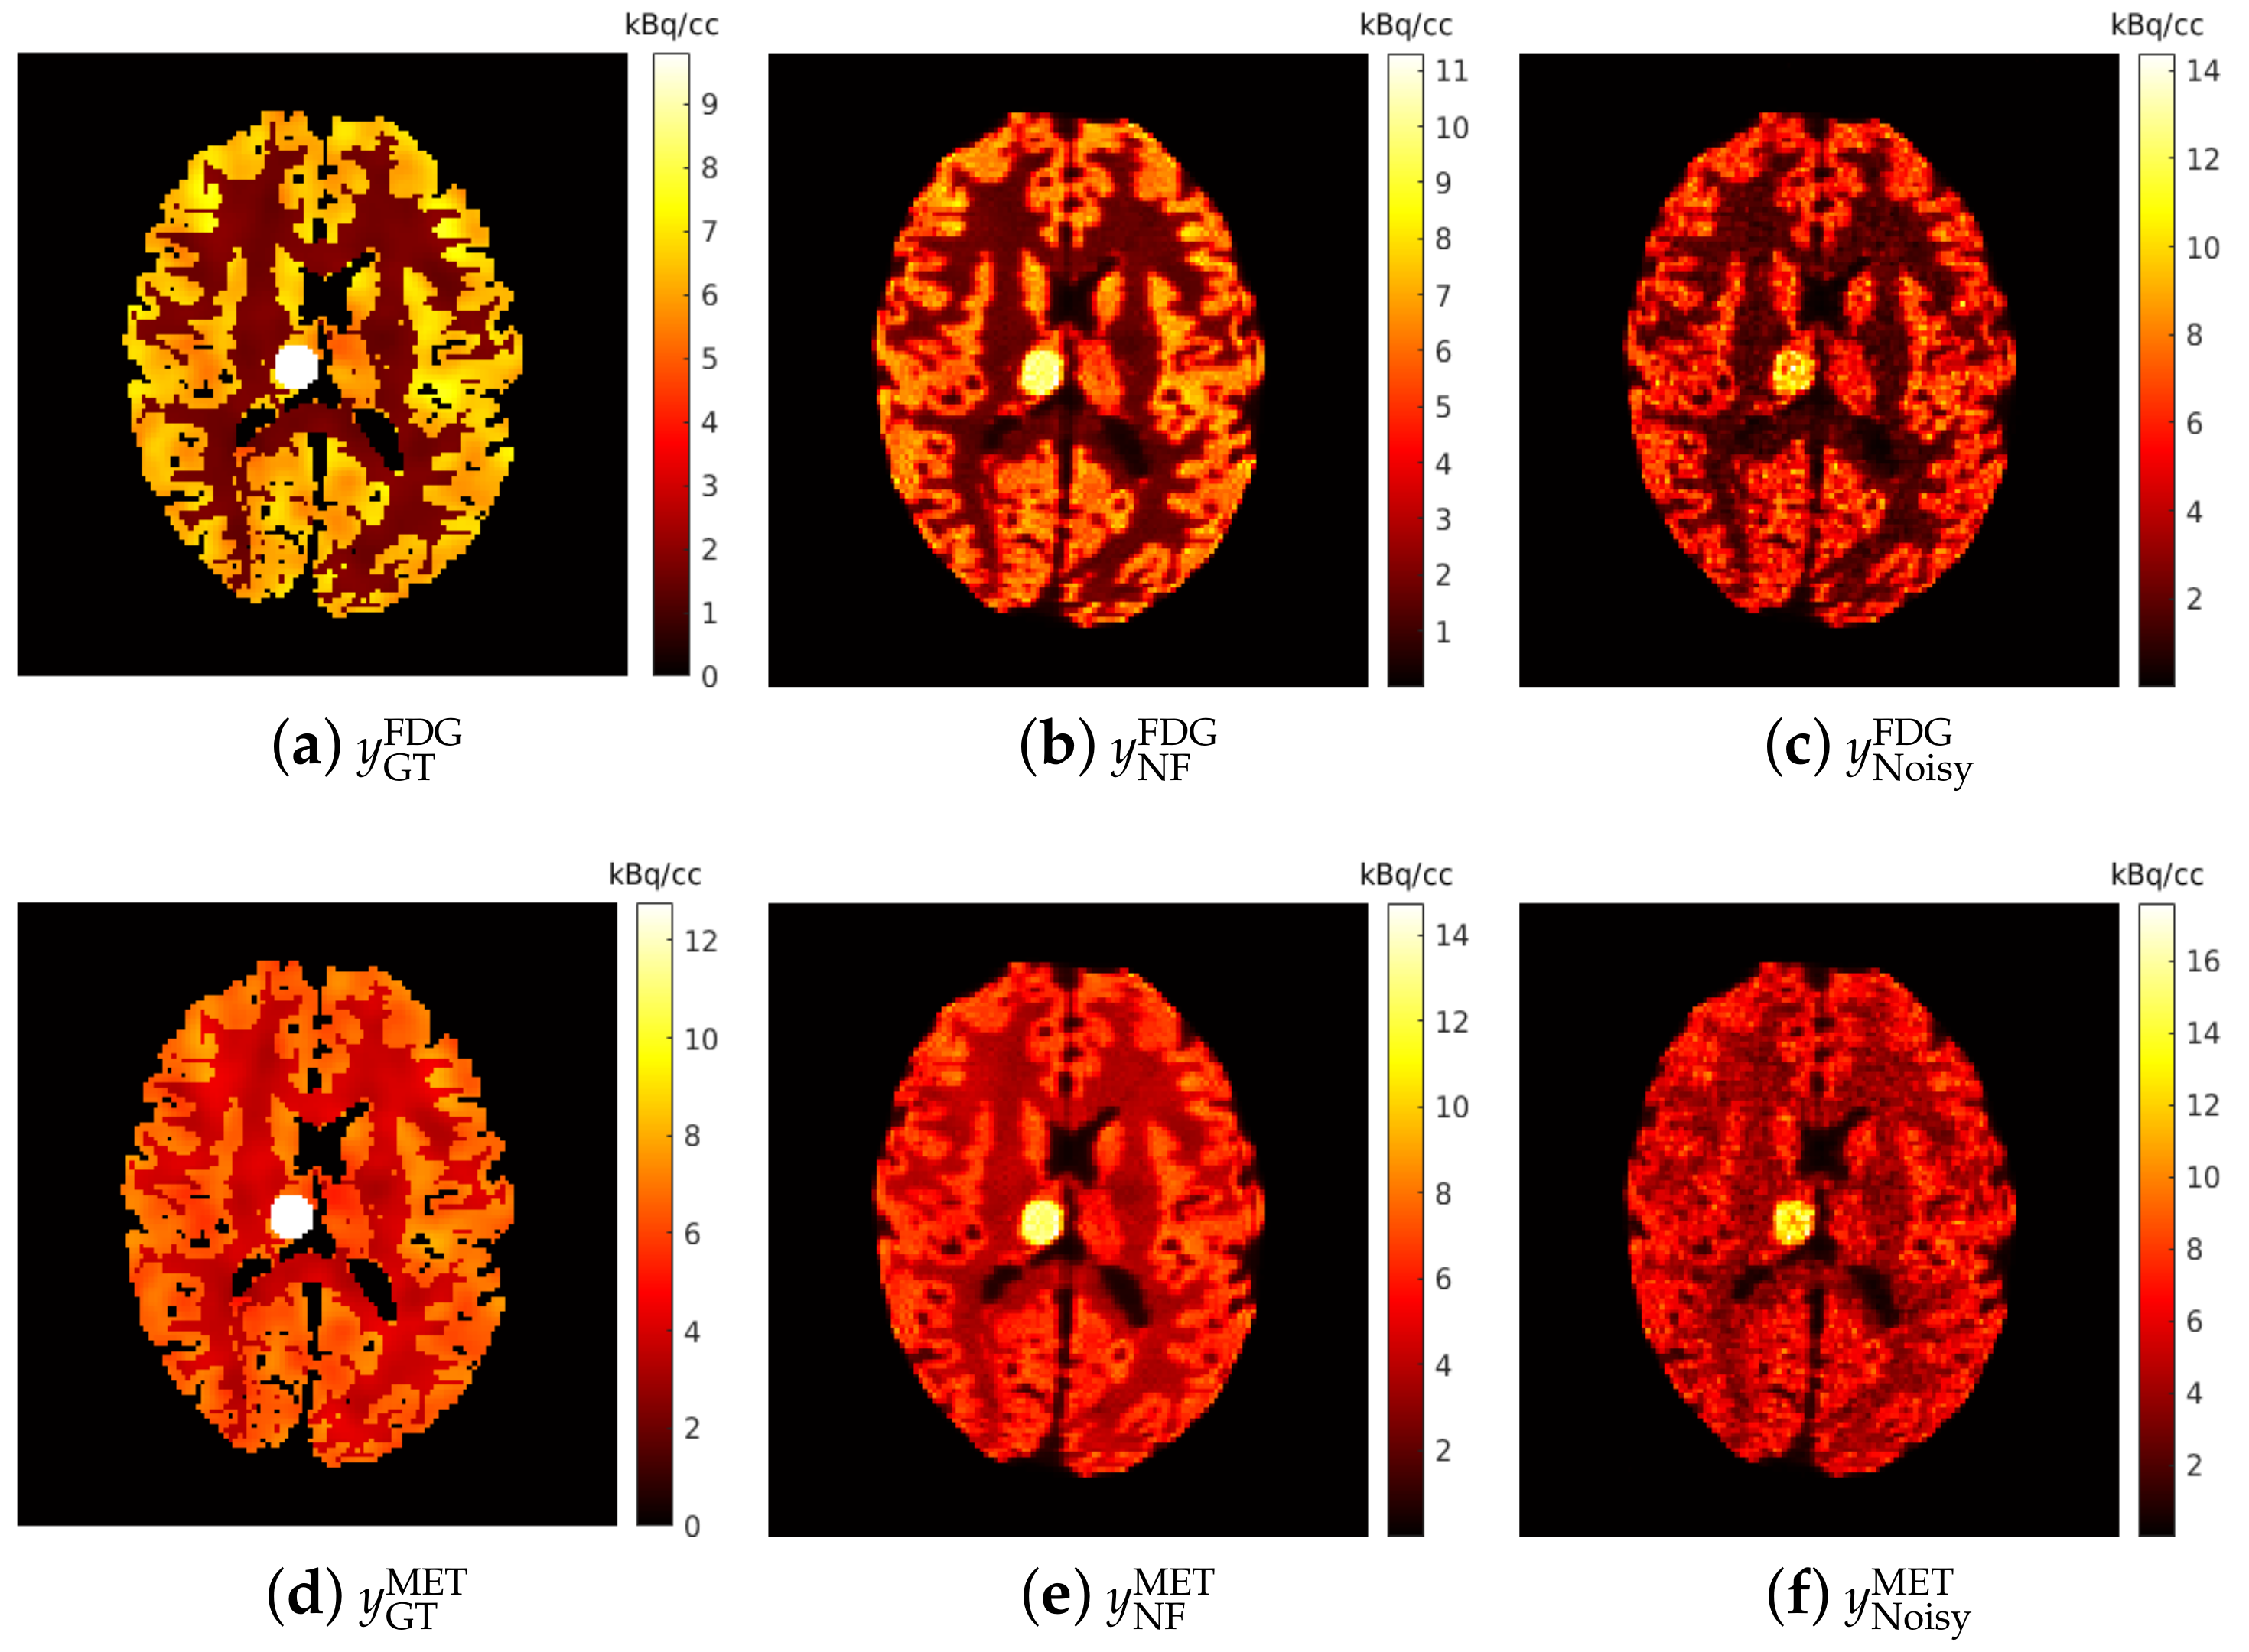

The simulated brain phantoms were reconstructed using the classic maximum-likelihood expectation maximization (MLEM) algorithm [58]. A total of 128 iterations were used for EM reconstruction to maintain the balance between bias and noise as suggested in [28,59]. Given that the PET scanner measures average activity concentration over time, the reconstructed dynamic dual-tracer images were further normalised by frame widths, e.g., for the mth frame, to obtain the (non-decay corrected) dual-tracer TACs of each voxel. The reconstructed single-tracer images were also normalised by 20 min static acquisition time to obtain the activity distributions. The reconstructed dynamic dual-tracer images and the reconstructed static single-tracer images were used as network inputs and training labels, respectively. Examples of reconstructed static single-tracer noisy MLEM images are shown in Figure 6c,f, together with the corresponding noise-free MLEM reconstructions (NF) (b,e) and the ground truths (a,d). When 2 days, the dual-tracer signals were entirely separated (reasons for which are discussed in Section 3.1), and thus two reconstructed dynamic single-tracer images were obtained, one for each tracer. In this case, the reconstructed dynamic single-tracer images (either FDG or MET) were employed as the network input. In this special case, the MSE loss is only applied to either FDG or MET, depending on the choice of the tracer considered in the network input. Notice that the decay correction cannot be performed in dual-tracer PET prior to separation because the proportion of each tracer (and hence its decay correction factor) is unknown prior to separation. While we do model decay, we do not seek to include decay correction in this present work.

Figure 6.

Brain phantom: an example of the simulated static single-tracer images (tracer activity distributions) for and : (a,d) ground-truth static images; (b,e) noise-free MLEM reconstructions; (c,f) noisy MLEM reconstructions.